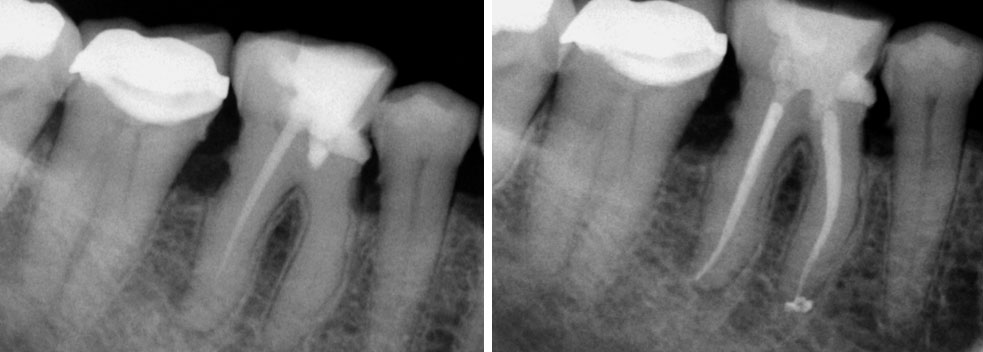

Broken instrument in the mesio-buccal root of the maxillary second molar.

Residual caries seen after temp removal.

After caries removal

Cotton pellets placed over the palatal and Disto-buccal orifices to prevent the instrument from slipping into those canals.

Fractured instrument in mesio-buccal canal

Fractured instrument removed with ultrasonics

Canals cleaned, shaped and obturated

Fiberglass-post and composite core placed

Post-op